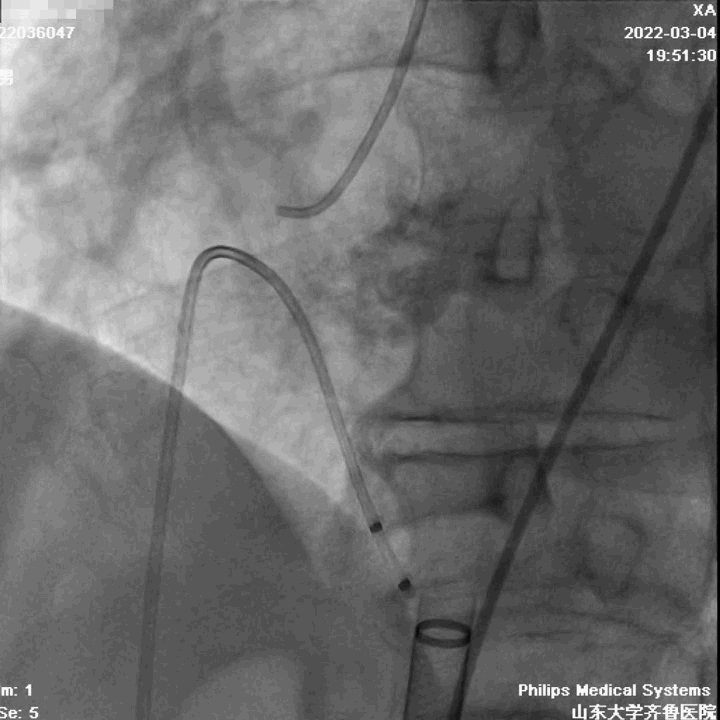

手术过程

第二例病人同样为高难度病例,Type1型L-R融合二叶瓣,钙化积分1300,瓣叶增厚、轻度钙化,钙化分布于瓣叶及左右瓣叶融合脊。

瓣环周长87.4mm,平均径27.1mm。LVOT周长90.5mm,平均径28.5mm。

瓣上4mm/6mm,预估可推开空间周长81.8mm/75.8mm。

在陈院长指导下,李传保主任团队顺利迅速完成了手术,目前病人恢复良好,均已出院。